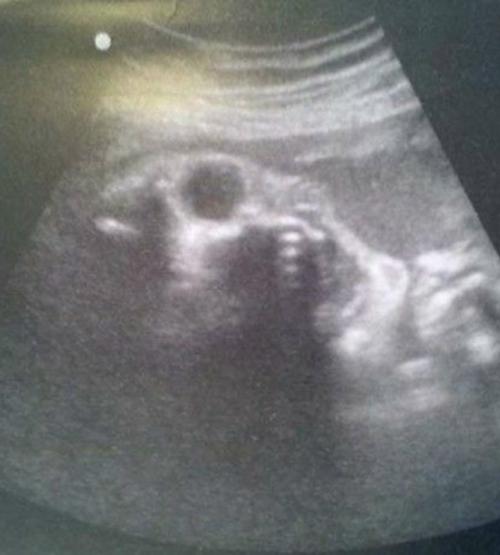

За девять лет я увидела на узи такое, что иногда хочется закрыть кабинет и уйти варить валерьянку. Дети в животе, конечно, милые … но не всегда. То кто-то машет мне, как будто баллотируется в мэры. То смотрит таким взрослым взглядом, будто уже знает, сколько стоит коммуналка. А иногда включаешь аппарат - и на тебя смотрит что-то, что больше похоже на трейлер к хоррору, чем на будущего малыша

. Родители белеют: "это нормально! А я стою, улыбаюсь и думаю: "ну почему именно на моей смене. Но вслух говорю: "Да всё Хорошо, Просто Ребёнок Репетирует Роль в Ужастике". Самое забавное - рождаются потом обычные, милые, пухлые. И ты смотришь на них и вспоминаешь снимок: "ну ты, конечно, артист …".